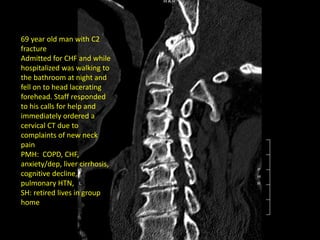

69 year old man with C2

fracture

Admitted for CHF and while

hospitalized was walking to

the bathroom at night and

fell on to head lacerating

forehead. Staff responded

to his calls for help and

immediately ordered a

cervical CT due to

complaints of new neck

pain

PMH: COPD, CHF,

anxiety/dep, liver cirrhosis,

cognitive decline,

pulmonary HTN,

SH: retired lives in group

home

69 year oldman with C2 fracture Admitted for CHF and while hospitalized was walking to the bathroom at night and fell on to head lacerating forehead. Staff responded to his calls for help and immediately ordered a cervical CT due to complaints of new neck pain PMH: COPD, CHF, anxiety/dep, liver cirrhosis, cognitive decline, pulmonary HTN, SH: retired lives in group home